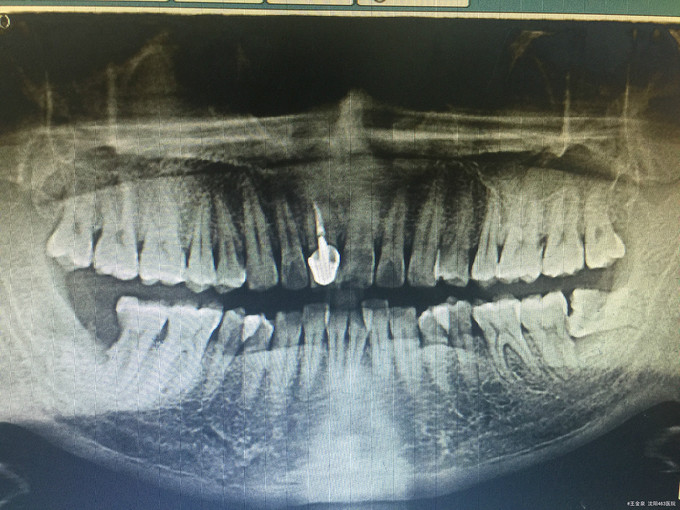

临床检查:47远中龋坏,探疼(+),冷(++),叩(-),松动度(-),牙周正常. 48未完全萌出, 辅助检查:X线示47远中龋坏累积髓腔,48近中水平阻生。

诊断:47牙髓炎,48阻生齿 治疗:经患者知情同意后,48拔除,47局麻去腐降牙合,开髓拔髓寻找根管口,建立直线通路,扩通根管,确定工作长度。S3/EDTA凝胶镍钛器械,低浓度次氯酸钠冲洗根管,预备至35/04,氢氧化钙诊间封药,一周后复诊,试主尖X线示恰充,试干根管,导AH-PLUS糊剂,VDW热压胶垂直加压根充,术后见根管恰充,暂封调合抛光。观察桩冠修复。